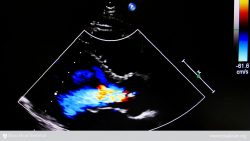

The procedure is performed with general anesthesia in a hybrid suite (which has both catheterization and surgical capabilities). A team of interventional cardiologists and imaging specialists, heart surgeons and cardiac anesthesiologists work together, using fluoroscopy and echocardiography to guide the valve to the site of implantation/replacement.